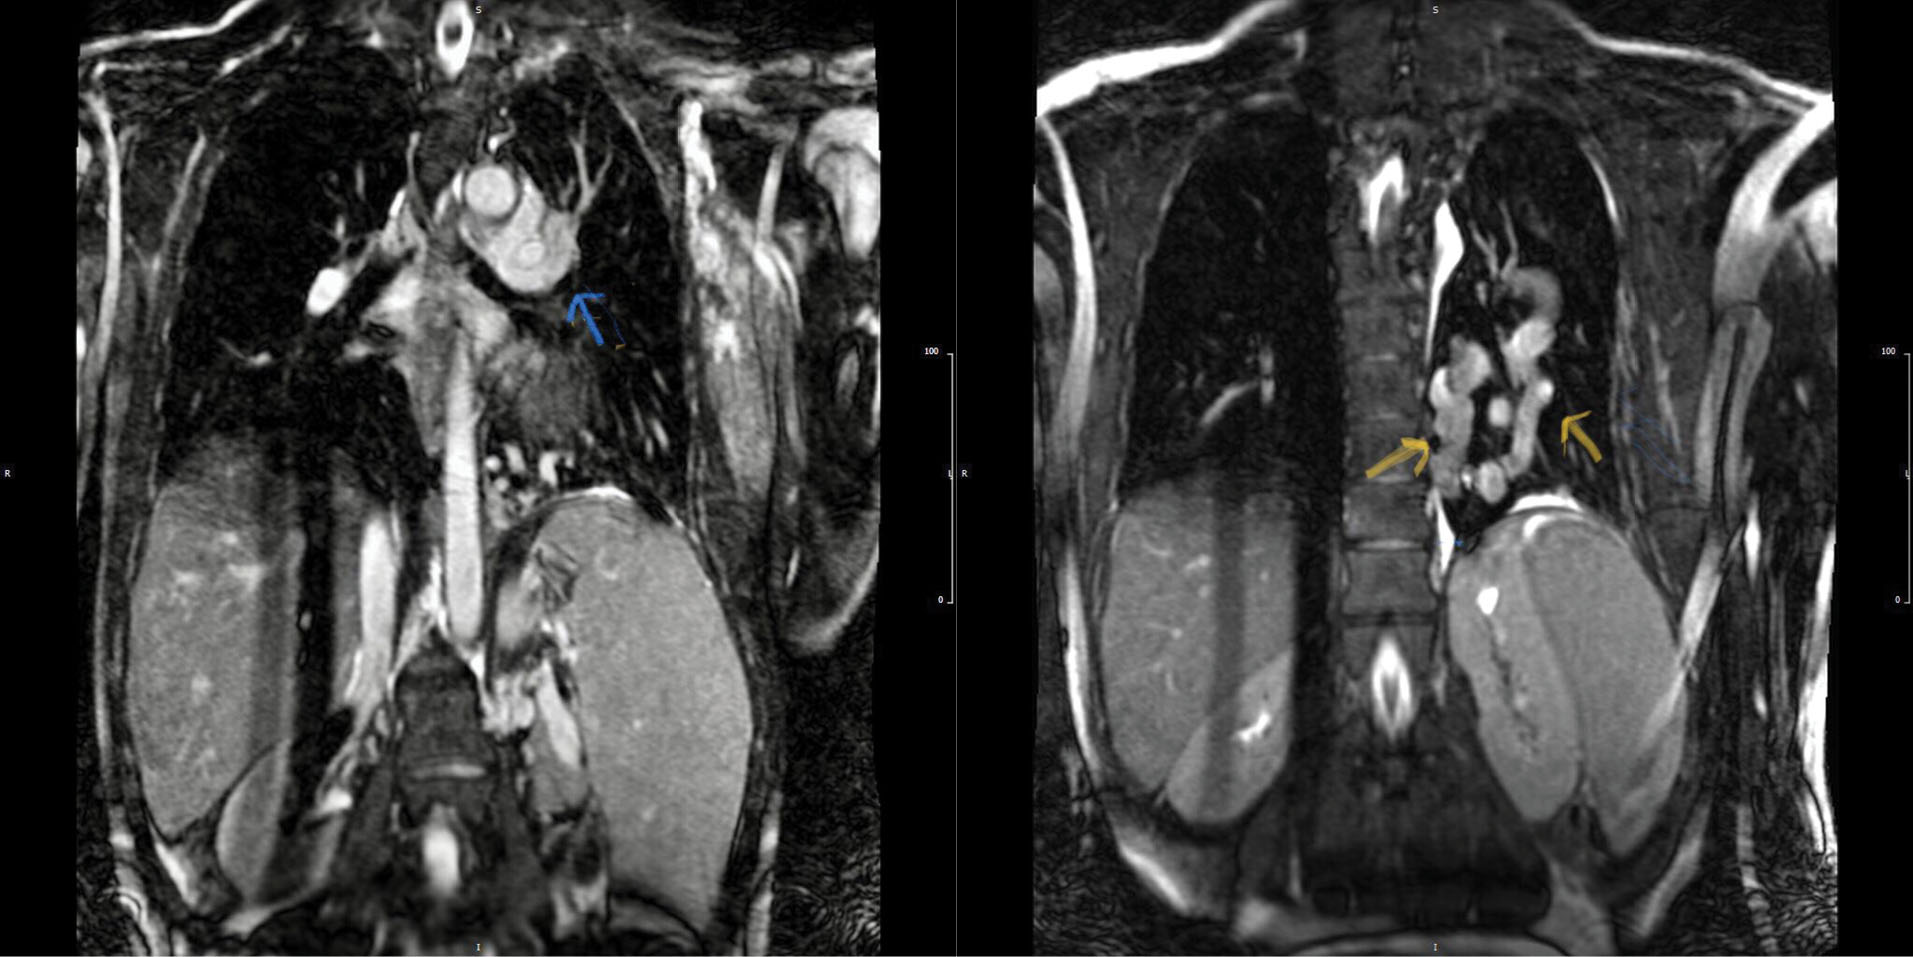

Hemoglobin concentration was 17g/dL. Electrocardiogram showed low voltage, poor R progression and left anterior hemiblock. Contrast trans-thoracic echocardiography (TTE) with an injection of agitated saline from left brachial vein showed a left-sided dilated para-aortic vessel including a blue color descending flow suggested left superior vena cava (LSVC) with a fast entrance of bubbles into the left atrium (). Finally, she underwent cardiac magnetic resonance imaging (CMR) due to cyanosis which revealed the presence of very engorged dilated left lower and left upper pulmonary veins with fistulous connection which left upper pulmonary vein (LUPV) connected to vertical vein and then into an innominate vein and finally SVC. The direction of flow was from SVC to left upper pulmonary vein, left lower pulmonary vein, and left atrium (LA). (). This Fistula was seen as collateral vessels connected proximally to the inferior aspect of innominate vein and distally to the left lower pulmonary vein. There were some connections between the ascending, and descending limbs of these tortuous venous collaterals and these direct connections between venous collateral vessels could explain fast pass of agitated saline into LA during TTE with contrast study and severe cyanosis of the patient. Probably this abnormal connection of LUPV to vertical vein (PAPVC) was not diagnosed before Fontan operation and developed gradually due to the pressure gradient in the Fontan circuit with connection to LLPV. This pressure gradient could result in further dilatation of vertical vein and prominence of collateral vessels which were connected to the inferior aspect of innominate vein. Thus, catheterization was performed () and Femoral vein was cannulated. We passed from IVC to fontan circuit, SVC, innominate and lastly vertical vein. In injection in vertical vein, we found severe engorged and tortoise pulmonary veins, then a long stiff exchange wire (260 cm) with a long LIFETECH delivery sheath 9F passed through fontan circuit to SVC, innominate vein and vertical vein. An ADO device 14*16 mm chosen and deployed at proximal of vertical vein (). After the detachment of device by vertical injection we confirmed proper position of device and small residual flow. The oxygen saturation immediately increased from 80% to 93%. In the first echocardiography performed after device closure, some contrast agents were entered into the left atrium through a right to left shunt, which indicates the presence of a residual shunt. This might be due to the delayed endothelialization of implanted device.

jcvtr-13-364-g002

Figure 2. Magnetic resonance angiography imaging (A)left upper pulmonary vein connection into the vertical vein (blue arrow) (B) tortuous and the large fistulous connection between left upper and lower pulmonary vein (yellow arrows)